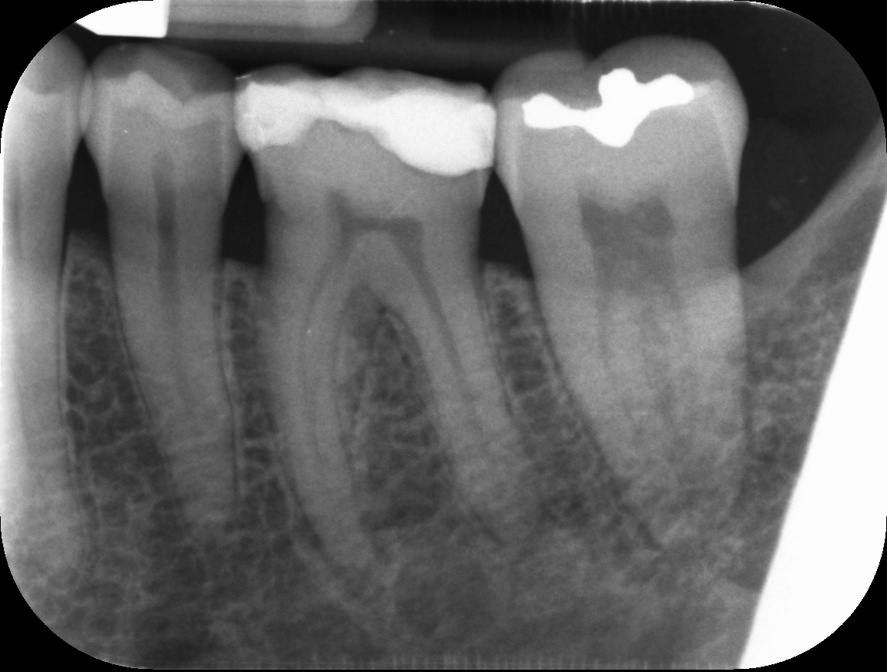

Endodontic Referrals

I am pleased to take endodontic referrals. Curved canals >30 degrees and potentially greater than 50 degrees can be negotiated. Sclerosed canals accessed. Post spaces prepared and the patient returned to you ready to restore.In most cases existing crowns, bridges and veneers can be retained with the endodontic access aesthetically restored after the full canal network has been treated.In the first instance I would prefer a radiograph and a brief list of patient expectations and a tooth history.

There are a number of ways to decide whether you need root canal treatment and the specific x-rays, scans and tests help diagnose your problem.An important sign is the type of pain you have been having with a tooth. It helps me decide if a tooth is in need of treatment and even if it saveable.

I really enjoy undertaking root canal treatments - rising to the challenge and helping people out of dental pain for the long term.I was privileged to be asked to speak at the 2016 BDA Conference, where I have a lecture about providing quality endodontic outcomes to patients, working as a generalist. Avoiding problems and pitfalls and maximising efficiency. One of the main matters that he covered was understanding that what is seen on plane radiography is utterly misleading and should not be the criteria by which a generalist continues treatment once it has been started.

At the 2016 BDA Conference, Thomas spoke about providing quality endodontic outcomes to patients, working as a generalist. Avoiding problems and pitfalls and maximising efficiency. One of the main matters that he covered was understanding that what is seen on plane radiography is utterly misleading and should not be the criteria by which a generalist continues treatment once it has been

started.